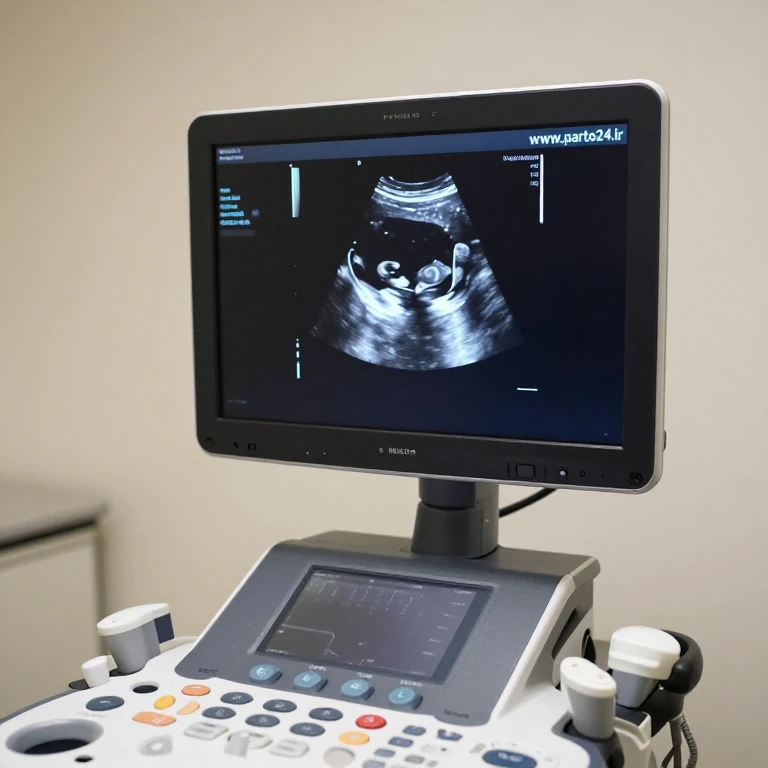

سونوگرافی جنسیت

سونوگرافی

1404/11/16

مقدمه: اشتیاق به دانستن جنسیت جنین سونوگرافی جنسیت یکی از هیجان انگیزترین مراحل دوران بارداری برای والدین است. ا...